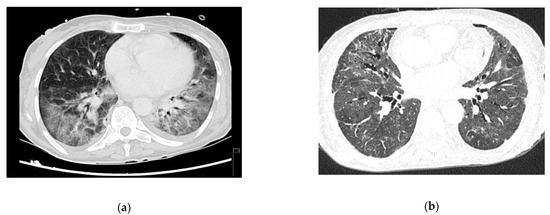

A 29-year-old male, HIV-positive since 2015, severely immunosuppressed that was lost to follow-up before starting ART. He presented in March 2019 at the emergency room (ER) with a one-day history of fever, shortness of breath and cough without providing information about his HIV status. Initial assessment showed polypnea of 30 cycles per minute (cpm), hypoxia, fever (39 °C), elevated C-Reactive Protein (CRP) and bilateral middle and lower zone air space opacities on chest X-ray. He was admitted to the ward and started empirical treatment for community acquired pneumonia (CAP). Two days later, he was transferred to the ICU with aggravated tachypnea (50 cpm), severe hypoxemia (paO2 49 mmHg) despite oxygen supplementation and pneumomediastinum, bilateral pneumothorax and diffuse ground-glass opacities on thoracic-CT scan (Figure 1a). The CD4+ lymphocyte count was 6/mm3 and the HIV-viral load was 18,200 copies/mL. All other microbiologic tests were negative. Treatment was then switched empirically to trimethoprim-sulfamethoxazole (TMP-SMX) 15 mg/kg of TMP each day in 3 takes plus corticosteroids for a presumed diagnosis of PJP. Later the diagnosis was confirmed by positive immunofluorescence as Pneumocystis jirovecii (P. jirovecii) in bronchoalveolar fluid (BAL).

Due to refractory hypoxemia and given the high probability of barotrauma, the patient was started on venovenous-ECMO(VV-ECMO) without prior tracheal intubation. He later needed intubation due to poor bronchial clearance of secretions and completed a 14 days-period of protective IMV in an attempt to reduce extra corporeal support. He completed 21 days of therapy with TMP-SMX plus corticosteroids according to recommended PJP treatment dosage (prednisolone 40 mg two times day for 5 days, then 40 mg each day for 5 days and after that 20 mg each day for 11 days). ART was started 15 days after the ICU admission, with a significant reduction in the viral load one month later (151 copies/mL). ECMO and protective IMV were maintained for 40 days, followed by 19 days of weaning off. The pneumomediastinum and bilateral pneumothorax were managed conservatively, and a new CT-scan performed 50 days later showed great improvement (Figure 1b). He was transferred to the ward after 69 days of ICU stay showing signs of significant myopathy. Three months after discharge, he was revaluated at outpatient care as fully recovered and with CD4+ lymphocyte count improvement (49/mm3).

Figure 1. Case 1 thoracic CT-scan at diagnosis (a) and follow-up (b).